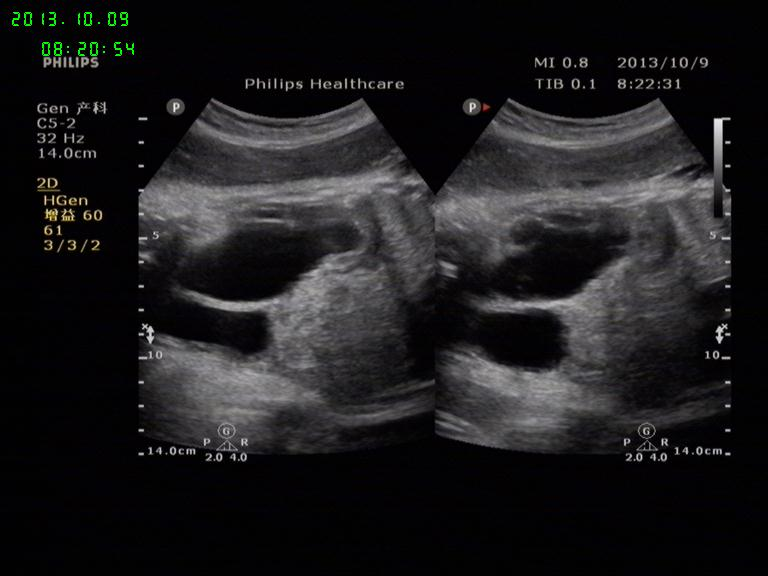

胎儿左肾积水

孕38周胎儿,左肾积水,右肾大小形态正常,羊水量AFI:20.5cm

右肾积水好多,曾经见过一例,产后1周做尿路造影考虑是重复肾

不好意思,第二张标记错了。